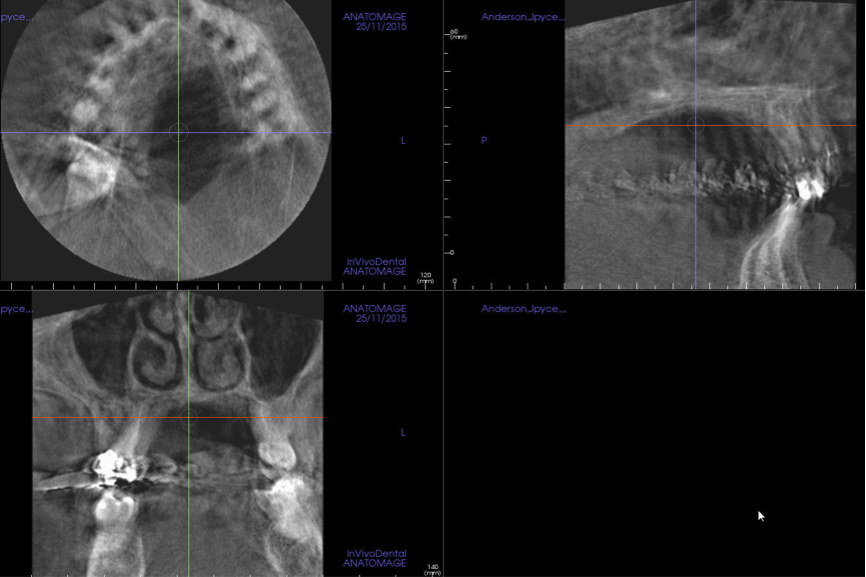

There is a documented link between radiologic image quality and diagnostic efficiency.6 In other words, a reduction in scan quality may obscure diagnostic information and compromise diagnosis. Patient motion during the scan acquisition and other image artifacts are the most important factors affecting image quality in CBCT studies. Patient motion is more likely to be seen in scans of either older individuals or children. The motion artifact can be recognized by the double margin it creates in the osseous boundaries, such as the maxillary and mandibular cortices. To limit motion artifacts, detailed patient instructions may be helpful as well as strict adherence to the manufacturer’s recommendations for scan acquisition (Figure 2). After the acquisition of a scan, the clinician should quickly review the image data for possible motion artifacts and retake the san if necessary.

(2.) CBCT orthogonal sections showing severe patient motion. Note the double margin of the maxilla and mandible, especially in the sagittal section (upper left). This scan has to be retaken.

Figure 2